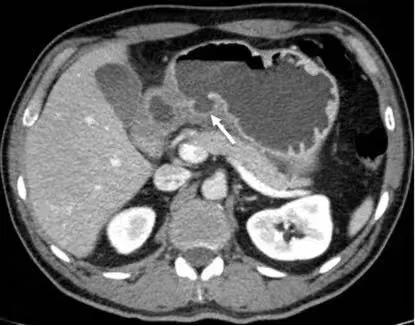

75 岁男性,急性胃炎,恶性呕吐就诊。CT 增强示胃壁弥漫性增厚,粘膜明显强化,可见粘膜下水肿。